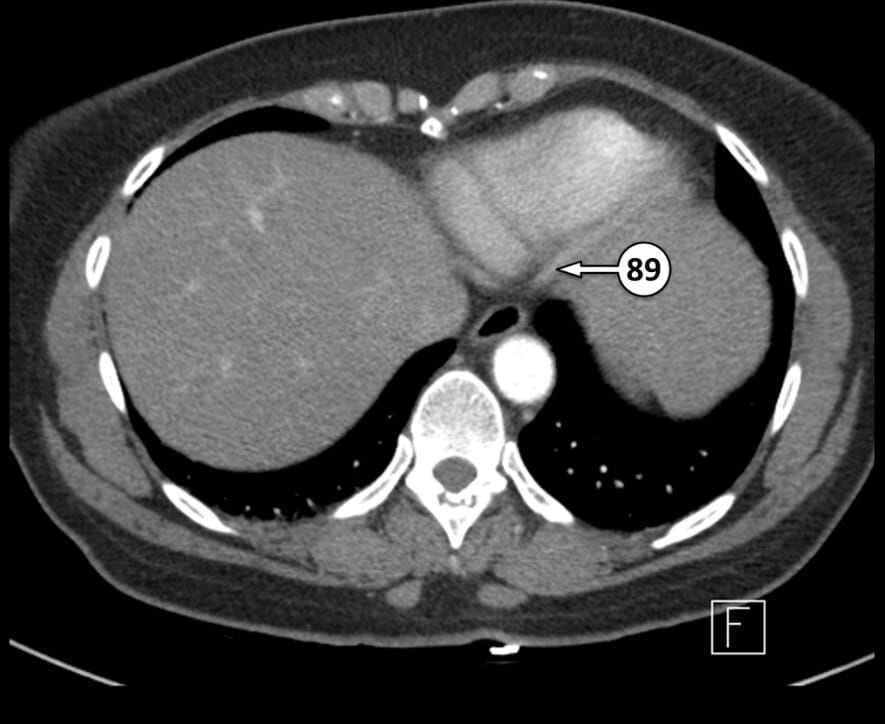

89. posterior descending artery (posterior interventricular artery)